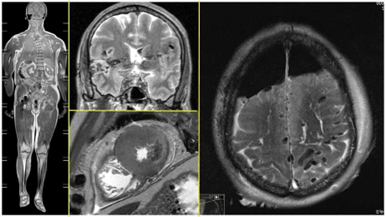

Over the past three decades, modern imaging techniques such as CT and MRI have become increasingly common in post-mortem forensic medicine. Both methods have specific strengths and weaknesses for post-mortem diagnostics. While forensic postmortem CT is now well established, the future of forensic post-mortem MRI is still uncertain. This presentation will highlight the fundamental strengths and weaknesses of postmortem forensic MRI, outline current examination standards, present some of our own research projects, and discusses potential future developments.